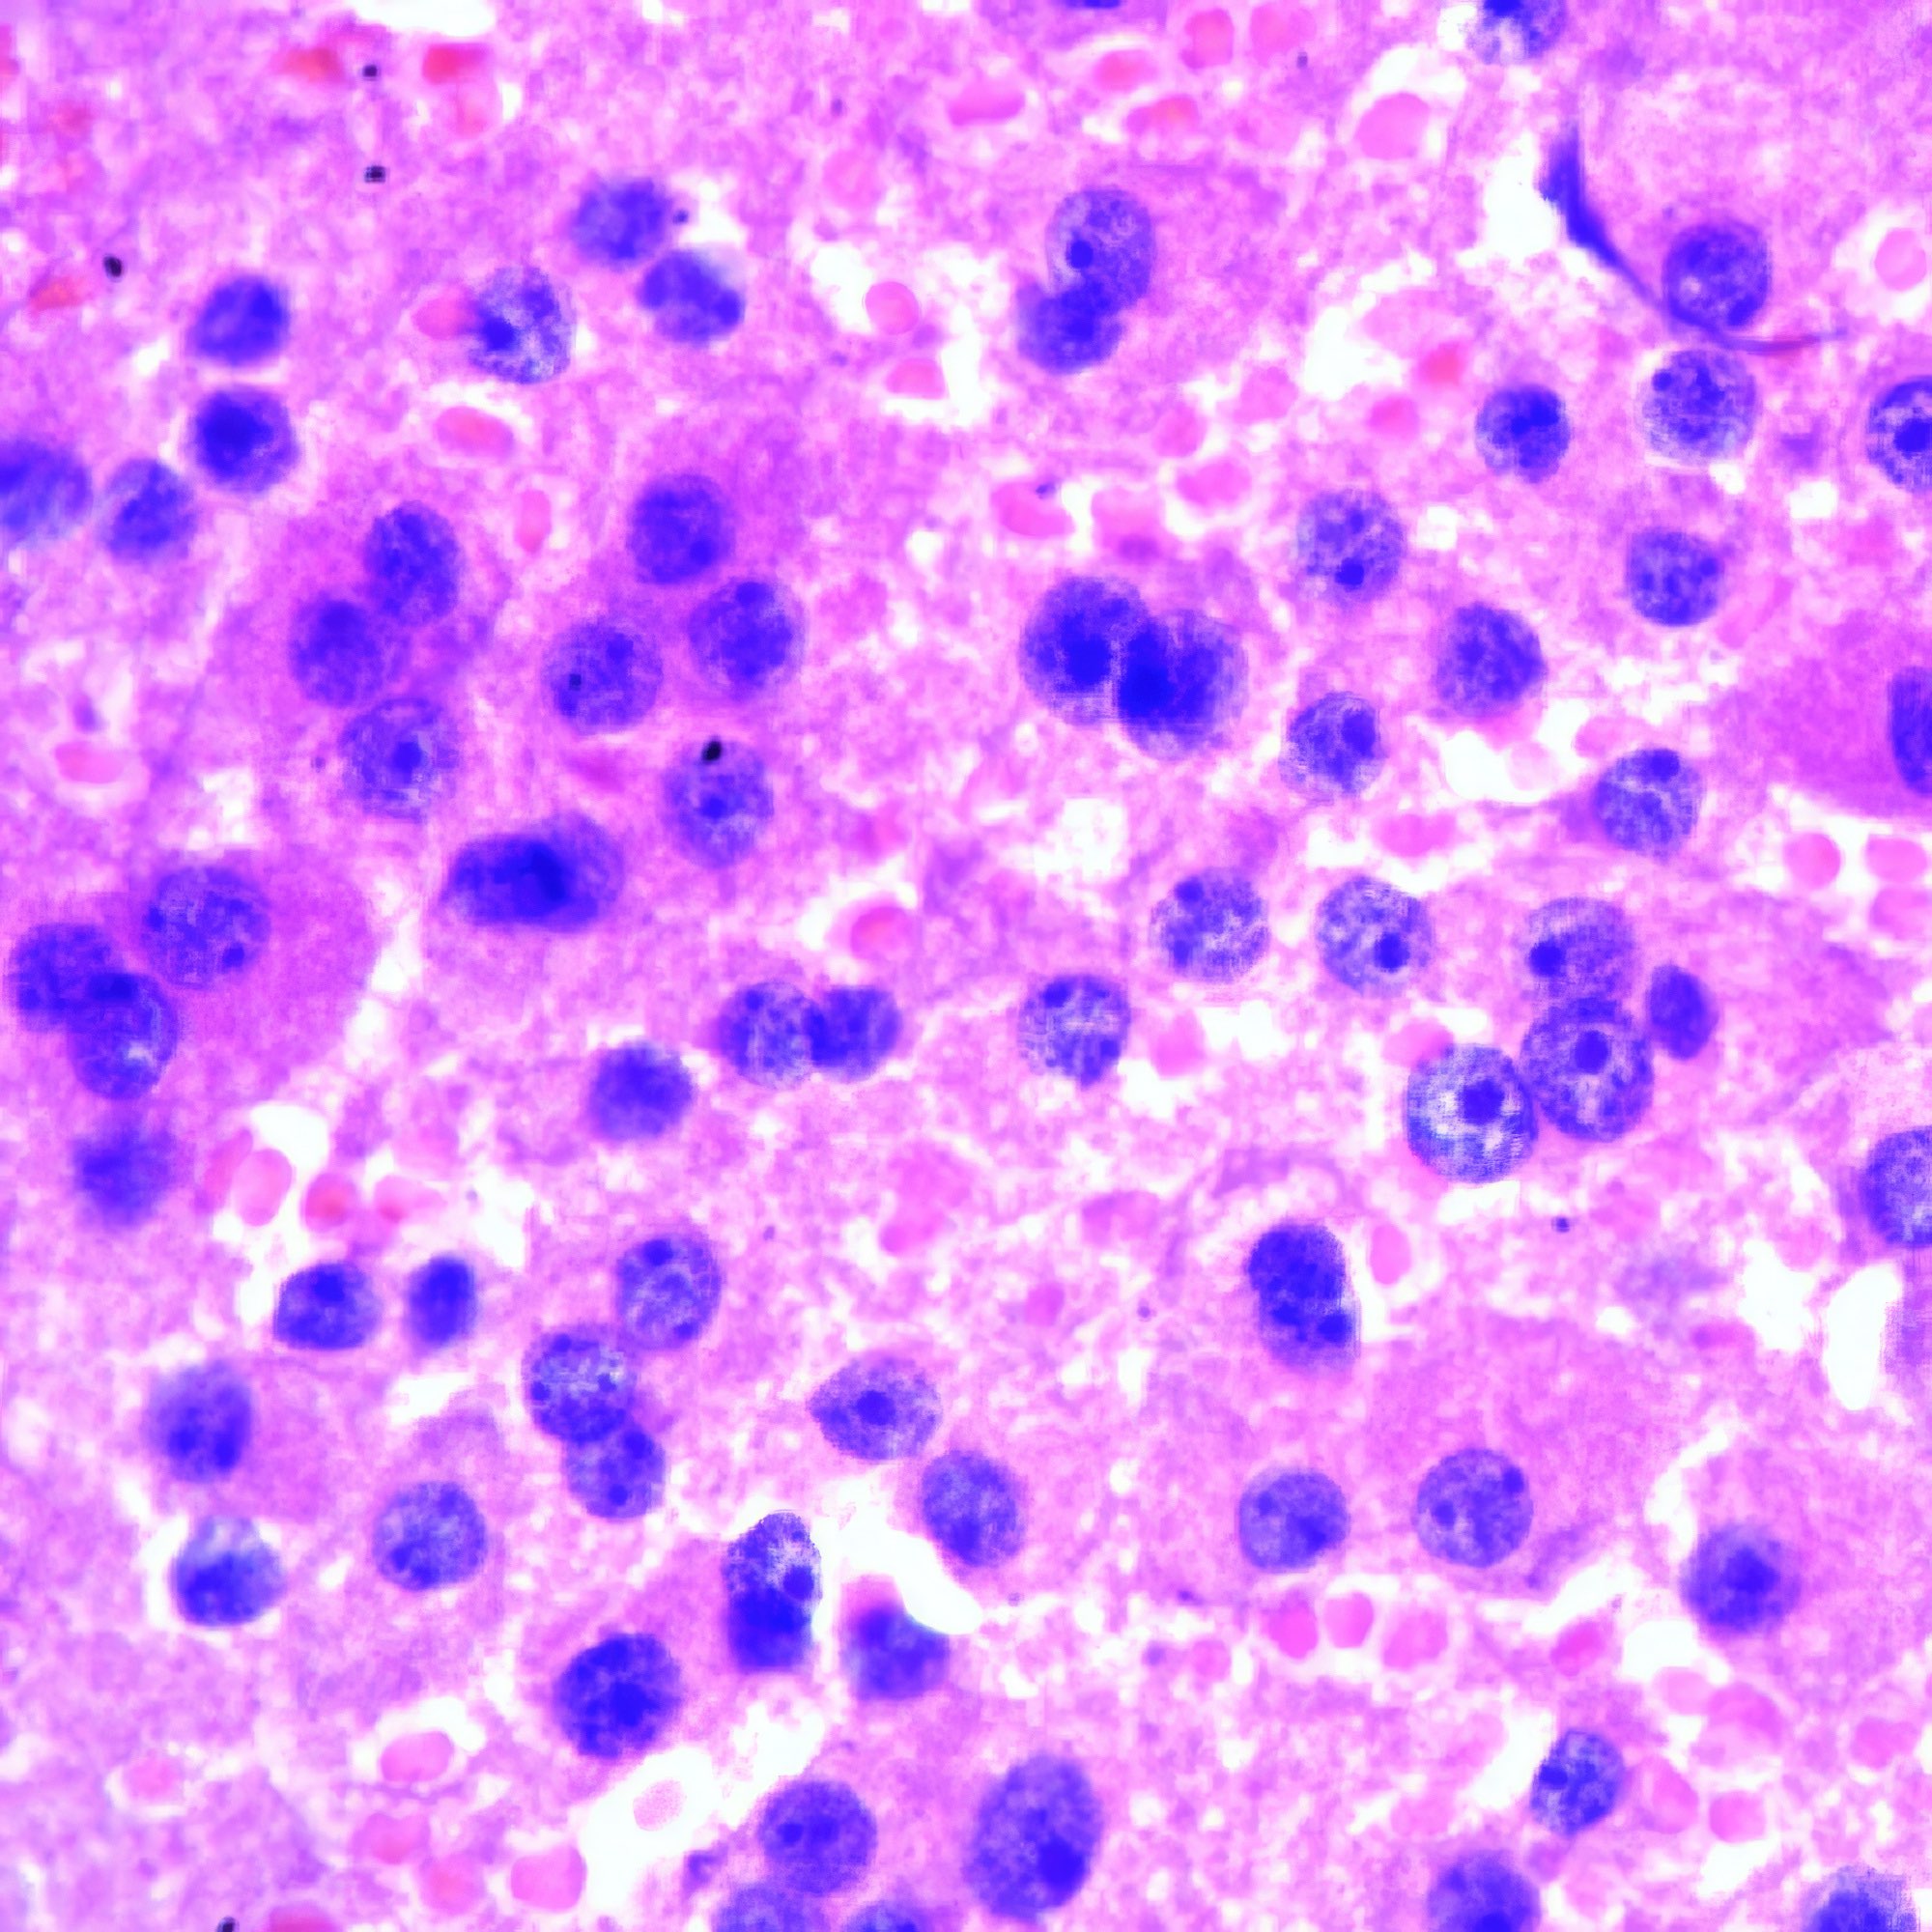

M, 55 Jahre, bemerkte seit 3 Monaten eine zunehmende inguinale Lymphknotenschwellung, der größte 3 x 4 cm messend, davon Feinnadelaspiration (FNA). Abbildung 1 bis 4: Verschiedene Areale des zytologischen Ausstrichs. Orig. 63x

Beschreibung

Die Bilder zeigen hochatypische Zellen. Deren überwiegend runde, teils auch ovalen Kerne variieren erheblich in ihrer Größe, sind deutlich grob strukturiert und enthalten meist ein oder mehrere prominente Nukleolen bzw. Chromozentren. Das Zytoplasma erscheint fragil. In jedem Bild finden sich auch Zellen mit pigmentbeladenem Zytoplasma. Der Ausstrichhintergrund enthält Blut und Zelldetritus, ebenfalls vermischt mit Pigmentkörnchen.

Kommentar

Der Patient beobachtete seit einem Jahr am Fuß eine pigmentierte Veränderung, die seit 3 Monaten auf 3 cm Durchmesser zunahm. Die prominente Atypie und die pigmenthaltigen Zellen sowie die ausgedehnte Metastasierung in die inguinalen Lymphknoten sind typisch für das Melanom. Eine Verwechslung des Melanin-Pigments mit Hämosiderin ist wegen der Zellatypie so gut wie ausgeschlossen. – Amelanotische Melanome zeigen oft eine weniger ausgeprägte Kernatypie und sind eher mit einem anderen Tumor zu verwechseln.